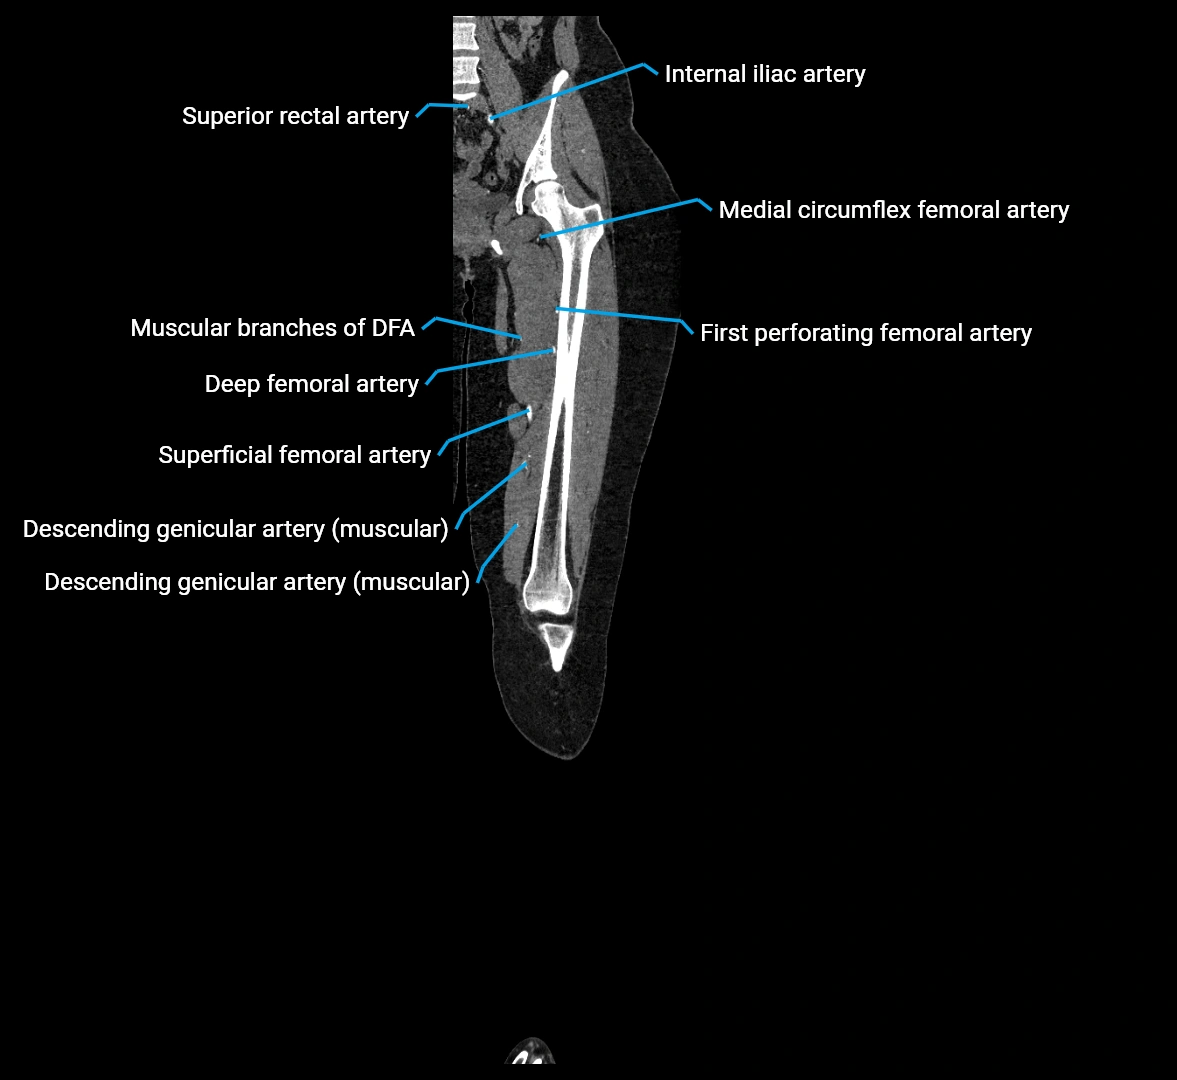

CT images

image

Contrast-enhanced CT (CTA):

• Gold standard for abdominal aortic imaging

• Provides excellent detail of lumen, wall, aneurysm, thrombus, and branch vessels

• Multiplanar and 3D reconstructions help in aneurysm measurement, stent graft planning, and dissection evaluation